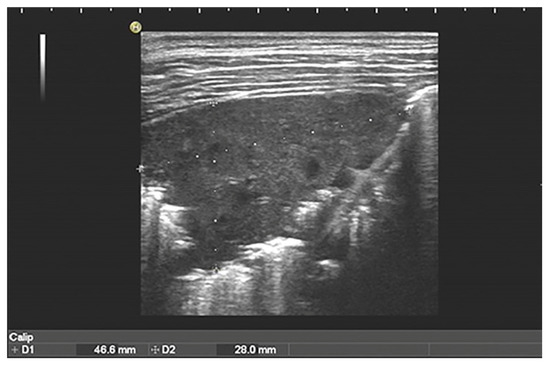

- Ruby, L.C.; Kadavigere, R.; Sheshadri, S.; Saravu, K.; Bélard, S. Pulmonary aspergilloma on transthoracic ultrasound. Infection 2021, 49, 1337–1340. [Google Scholar] [CrossRef]

- Alamdaran, S.A.; Heidarzadeh, H.; Zavvar, N.; Badlee, Z.; Jaberi, M.; Ghasemi, A. Presentation of Sonographic Features of Pulmonary Invasive Fungal Disease in Six Children with Leukemia. Int. J. Pediatr. 2021, 9, 13203–13211. [Google Scholar] [CrossRef]

- Liu, J.; Ma, H.R.; Fu, W. Lung Ultrasound to Diagnose Pneumonia in Neonates with Fungal Infection. Diagnostics 2022, 12, 1776. [Google Scholar] [CrossRef]